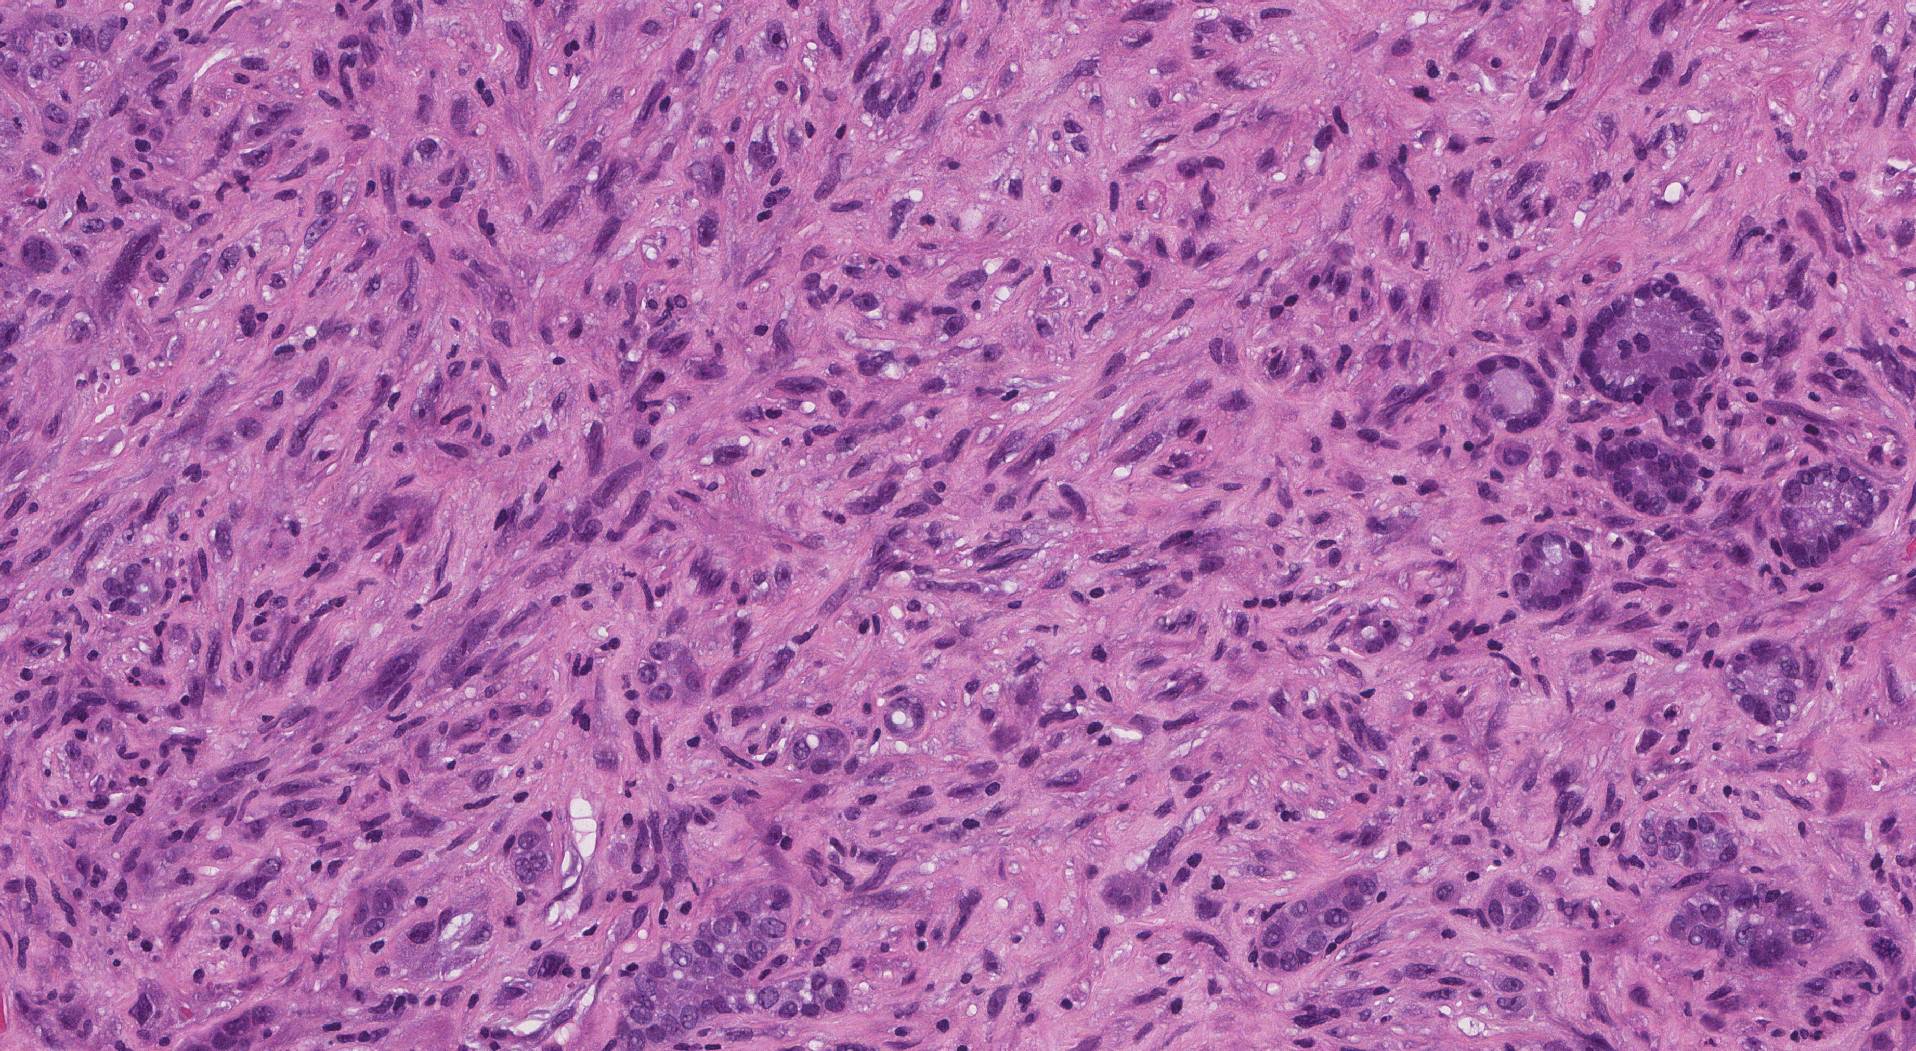

Alla diagnosi, la maggior parte dei pazienti presenta malattia localmente avanzata o metastatica. La biopsia con analisi molecolare è oggi imprescindibile: l’identificazione di mutazioni target (BRAF V600E, RET, NTRK, ALK) consente l’accesso a terapie mirate efficaci. La TC cervico-toracica, la PET/TC e la valutazione della via aerea sono parte integrante della stadiazione e della pianificazione terapeutica.